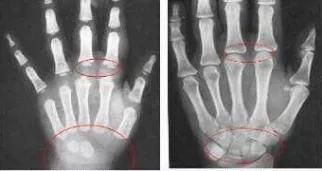

骨骺线完全闭合的20岁成年人骨龄片(左)骨骺线未闭合的7岁儿童骨龄片

了解一下骨骺线一旦闭合基本上没有长高空间了